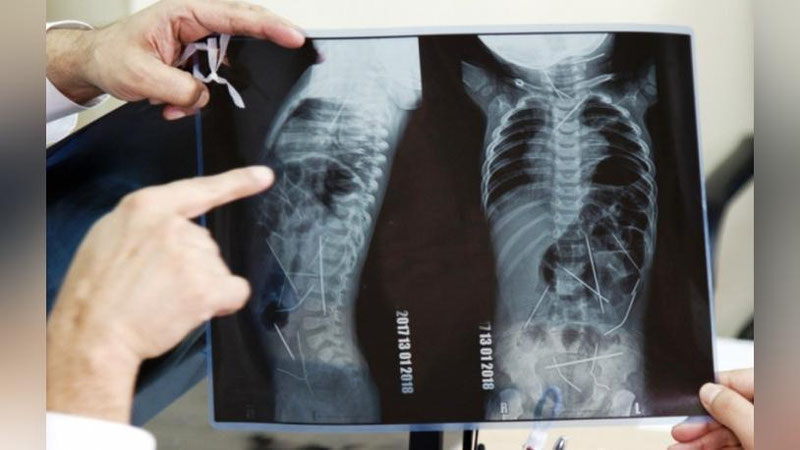

Январ ойида ижтимоий тармоқларда энг кўп муҳокама бўлган, фойдаланувчиларни чуқур ҳаяжонга солган хабар — танасидан 16 та игна ва сим бўлаги топилган чақалоқ тақдири атрофидаги фикр-мулоҳазалар ҳали-ҳамон поёнига етган эмас.

Шифокорнинг айтишига қараганда, боланинг танасида яна 3та игна қолган. Лекин улар соғлиқ учун хавф туғдирадиган жойда жойлашмагани туфайли, ҳозирча уларга тегилмайди. Бола 5-6 ёш бўлгандан кейин, керак бўлса, улар ҳам олиб ташланиши мумкин. Бундай вазиятлар олдин ҳам бўлган. Ҳаттоки 22та нинани ютган бемор ҳам тиббий элак ёрдамида, операциясиз даволанган.